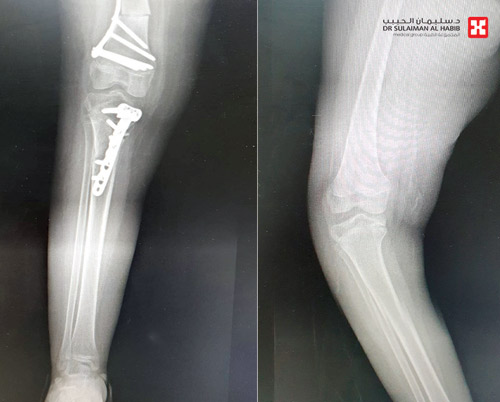

ذكر ذلك د.علاء محمد حمدان استشاري جراحة العظام رئيس الفريق الطبي المعالج، وقال إن المريضة راجعت المستشفى برفقة أهلها، وهي تشتكي من صعوبة شديدة في الوقوف والمشي، بسبب التقوس الشديد في الساقين مصحوبا بعدم الاتزان أثناء المشي، حيث أجريت لها حزمة من الفحوصات كالأشعة السينية والأشعة المقطعية والتي كشفت النتائج عن وجود تقوس يزيد على «40» درجة.

وأخضع الفريق الطبي الحالة إلى الدراسة على ضوء المعطيات التي قدمها التشخيص الدقيق، وخلص إلى أنها بحاجة إلى التدخل الجراحي، وقد أخضعت المريضة لعملية مزدوجة تم فيها تعديل التقوس في عظمتي الفخذ والساق وتثبيت محل التعديل بشرائح خاصة، وتكللت العملية التي استغرقت «3» ساعات بالنجاح، وغادرت المستشفى بحالة صحية ومعنوية جيد بعد 3 أيام من العملية.

ووصف د.علاء حمدان العملية بأنها تميزت بالدقة من حيث درجة ومكان التعديل، وحافظت على مفصل الركبة وأعادته إلى شكله الطبيعي، موضحاً أن المريضة عندما عادت للمتابعة في عيادة العظام، أجريت لها صور أشعة أكدت نتائجها التئام العظام، وتخلصت المريضة بشكل تدريجي من كافة الأعراض السابقة وعادت لممارسة حياتها بصورة طبيعية، والآن بعد مضي نحو «6» أسابيع من العملية استعادت القدرة على المشي، وستخضع لبرنامج علاج طبيعي تأهيلي لتقوية العضلات.